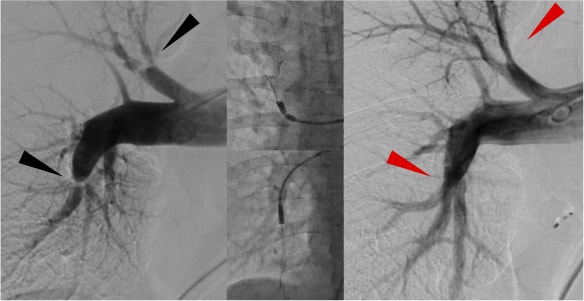

CTEPHとは慢性血栓塞性肺高血圧症(Chronic thromboembolic pulmonary hypertension)の略であり、肺血管内に血栓が形成され慢性化した状態です。治療法には、薬物療法、また中枢型では外科的な手術(肺動脈内膜剥離術)があります。当院では末梢型では埼玉県立循環器呼吸器病センターのBPA指導医のもとで修業を積んで経皮的肺動脈形成術(Balloon pulmonary angioplasty:BPA)を行えるようになりました。

CTEPHではカテーテル治療(BPA)により

息切れや呼吸困難が緩和されます